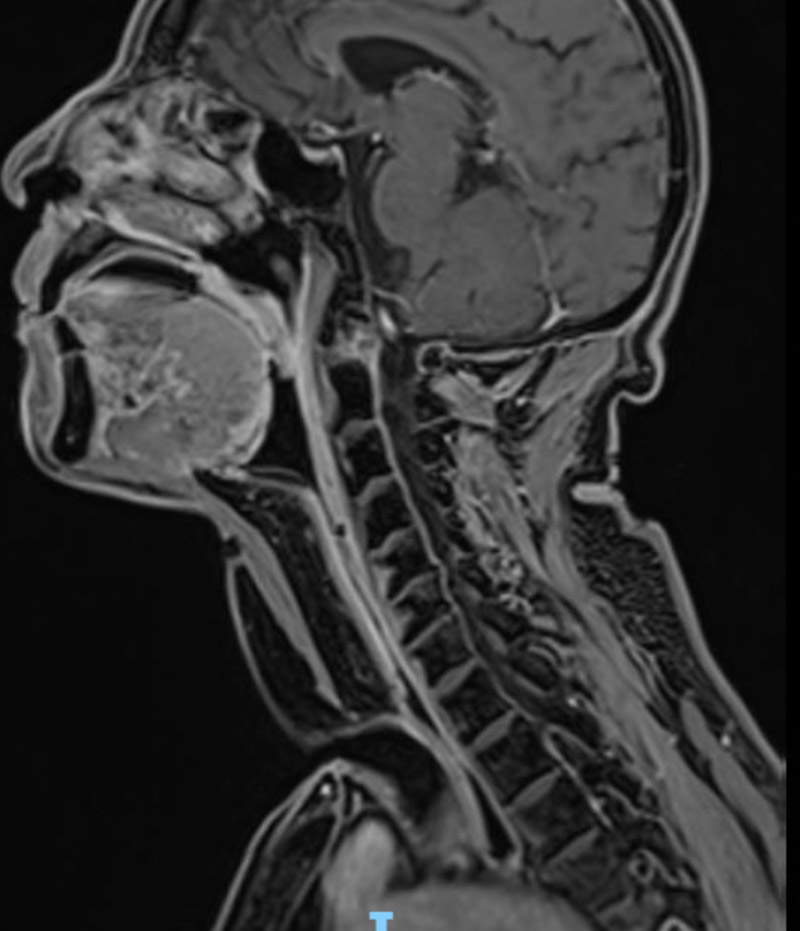

經(jīng)檢查發(fā)現(xiàn),患者喉癌已侵犯舌根、咽喉后壁、食管上端,病灶范圍廣。因放療無(wú)法控制病情,最終頭頸腫瘤MDT團(tuán)隊(duì)決定為其實(shí)施全喉切除+咽后壁、食道上段皮瓣修復(fù)術(shù)。

柳州市人民醫(yī)院耳鼻咽喉科頭頸腫瘤組專(zhuān)家朱漢平副主任醫(yī)師介紹,咽喉是生命重要通道,在社會(huì)交往和情感表達(dá)發(fā)揮重要作用,因此咽喉部腫瘤的治療不僅需要考慮腫瘤的根治,還要兼顧咽喉功能的保留。對(duì)于中晚期的喉部惡性腫瘤,根據(jù)其腫瘤范圍,需要個(gè)體化靈活應(yīng)用各種開(kāi)放術(shù)式,盡可能多地保留喉的支架結(jié)構(gòu)、功能單位和正常黏膜,以求最大限度地保留患者的吞咽、發(fā)音功能,減少術(shù)后并發(fā)癥,從而提高患者生存質(zhì)量。對(duì)于術(shù)后局部組織缺損較大的患者,還需要運(yùn)用各種類(lèi)型的皮瓣修復(fù)手術(shù)對(duì)缺損部位進(jìn)行修復(fù)。

手術(shù)如期進(jìn)行,耳鼻咽喉科手術(shù)團(tuán)隊(duì)術(shù)中仔細(xì)分離切除腫瘤,取胸部復(fù)合肌皮瓣組織,同時(shí)修復(fù)患者頸部皮膚、下咽和食管上段缺損。這樣一來(lái),既保證了患者正常的飲食功能,又保證了患者的頸部外觀。